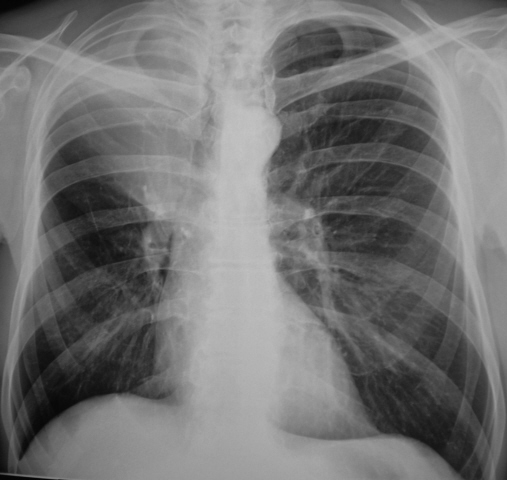

Иллюстрация 3. Поднят «архив». Цифровая флюорограмма за 2007 год.